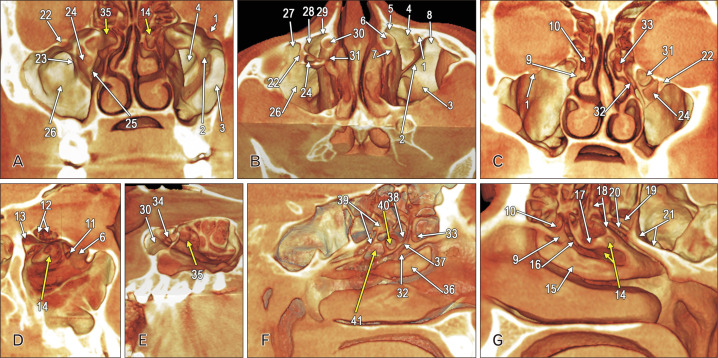

Pneumatisation of the maxillary sinus (MS) is variable. The archived cone-beam computed tomography file of a 54-year-old female was retrospectively evaluated anatomically. Nasal or retrobullar recesses of the MSs (NRMS) were found. The MSs were bicameral. NRMSs extended from the postero-lateral chambers of the MSs into the lateral nasal walls. The right NRMS was reached superior to the middle turbinate and the ethmoidal bulla was applied on its anterior side. The left NRMS had two medial pouch-like ends, one beneath the ethmoidal bulla and the other on the anterior side of the basal lamella of the middle turbinate. Additional anatomical findings were the uncinate bulla, infraorbital recesses of the MS, maxillary recess of the sphenoidal sinus, and atypical posterior insertions of the superior nasal turbinates, maxillo-ethmoido-sphenoidal and ethmoido-sphenoidal. The NRMS is a novel finding and could lead to erroneous endoscopic corridors if not documented before the interventions.

上颌窦(MS)的充气情况多种多样。我们对一名 54 岁女性的锥形束计算机断层扫描档案进行了回顾性解剖评估。发现了上颌窦的鼻腔或髓后凹陷(NRMS)。多发性硬化症为双侧。NRMS 从 MS 的后外侧腔延伸至鼻侧壁。右侧 NRMS 位于中鼻甲上方,乙状鼓室位于其前侧。左侧 NRMS 有两个内侧袋状末端,一个位于乙状鼓室下方,另一个位于中鼻甲基底层前侧。其他的解剖学发现包括钩状鼓室、MS 的眶下凹陷、蝶窦的上颌凹陷以及上鼻甲、上颌-乙状-蝶窦和乙状-蝶窦的非典型后方插入。NRMS 是一项新发现,如果不在干预前记录下来,可能会导致错误的内窥镜走廊。